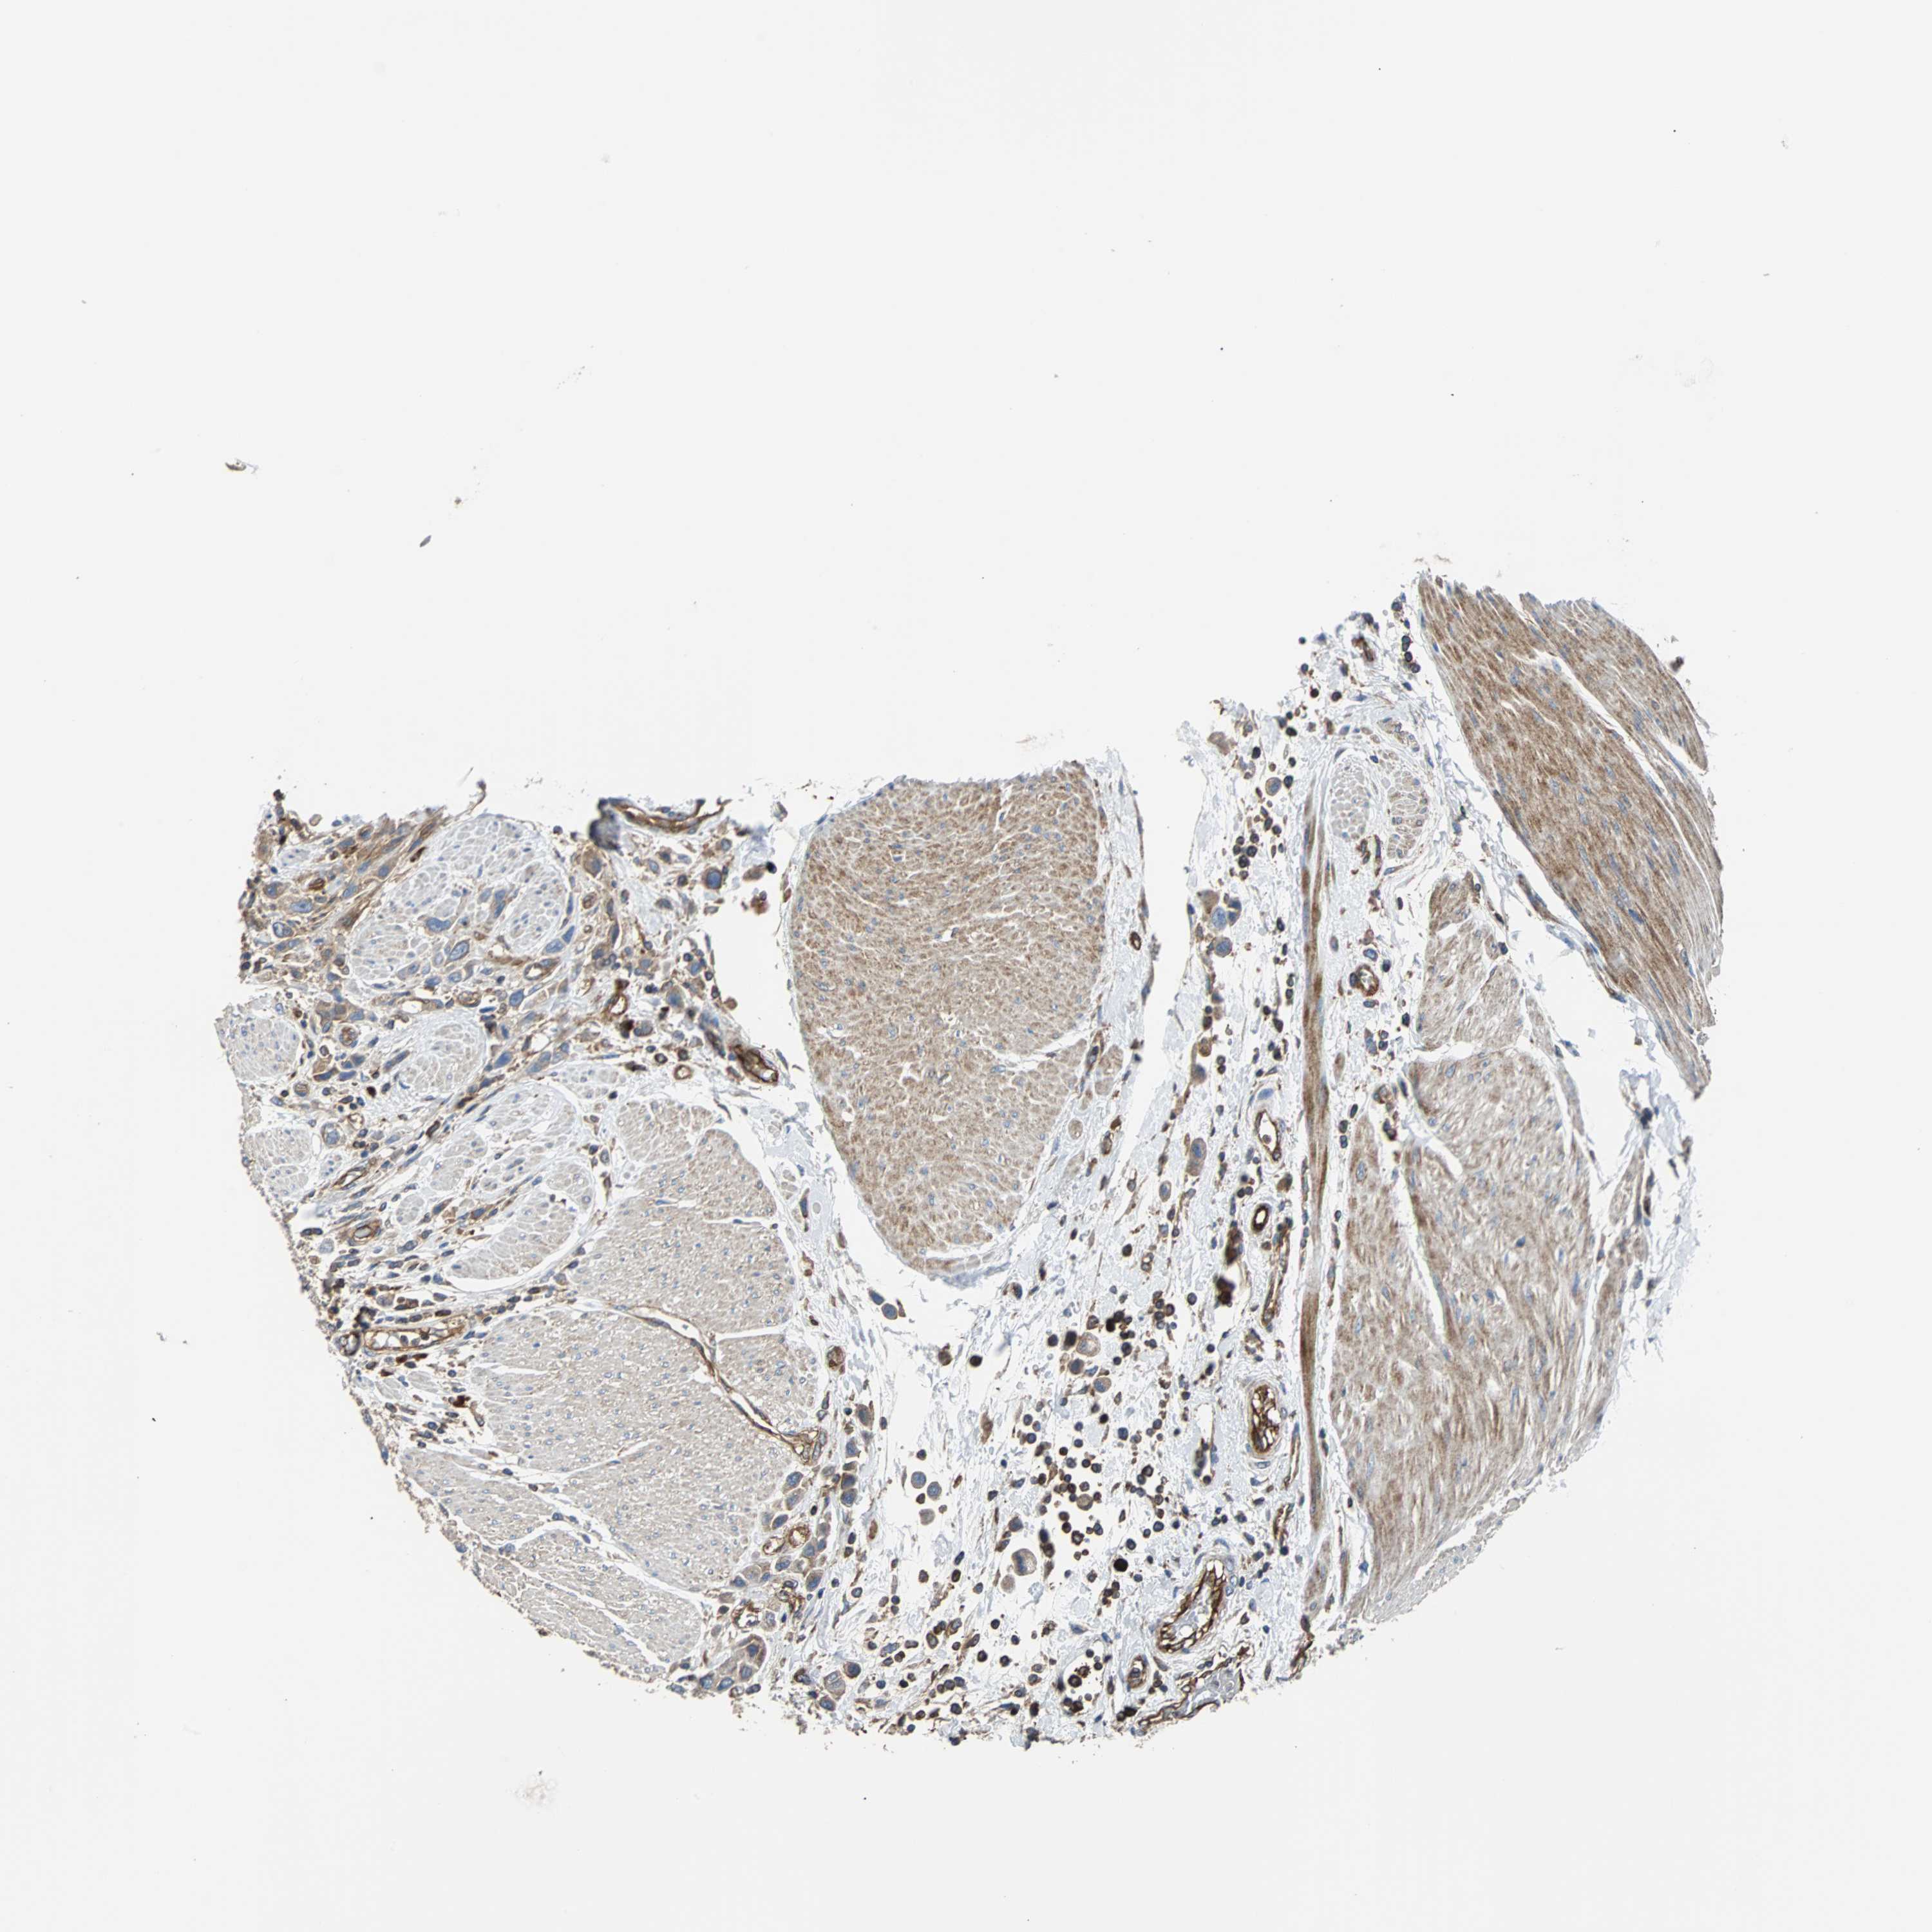

UROTHELIAL CANCER - Protein expressioni

A mouse-over function shows sample information and annotation data. Click on an image to view it in a full screen mode. Samples can be filtered based on level of antibody staining by selecting one or several of the following categories: high, medium, low and not detected. The assay and annotation is described here.

Note that samples used for immunohistochemistry by the Human Protein Atlas do not correspond to samples in the TCGA dataset.

Antibody stainingi

Antibody staining in the annotated cell types in the current human tissue is reported as not detected, low, medium, or high, based on conventional immunohistochemistry profiling in selected tissues. This score is based on the combination of the staining intensity and fraction of stained cells.

Each image is clickable and will lead to virtual microscopy that enables deeper exploration of all samples and also displays staining intensity scores, fraction scores and subcellular localization as well as patient and tissue information for each sample.

Antibody HPA020099

Antibody HPA020100

Antibody CAB004280

Staining

High

Medium

Low

Not detected

Intensity

Strong

Moderate

Weak

Negative

Quantity

>75%

75%-25%

<25%

None

Location

Nuclear

Cytoplasmic/membranous

Cytoplasmic/membranous,nuclear

Urothelial carcinoma, Low grade

Urothelial carcinoma, High grade